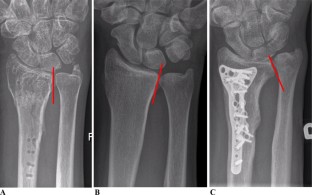

Fig. 2